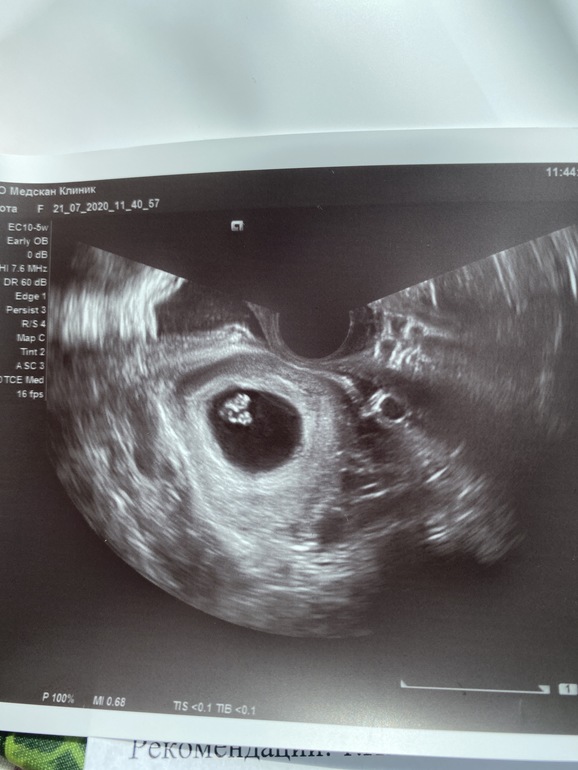

Все хорошо, нам 7 недель и 2 дня) плодное яйцо 26мм, КТР 10 мм, ЧСС 176 ударов 🥰🥰🥰🥰

Аномалия у меня, матка в форме сердца (двурогая).

Отслоек нет! 😍😍😍